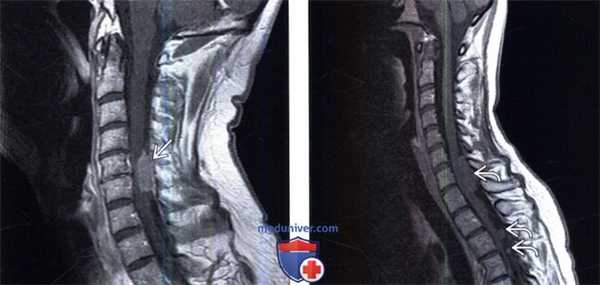

(Слева) Сагиттальный срез, Т1-ВИ: патологическое диффузное усиление сигнала СМЖ на всем видимом участке дурального мешка. При дальнейшем обследовании у пациента диагностирован карциноматоз мягких мозговых оболочек вследствие диссеминации интракраниальной глиомы.

(Справа) Сагиттальный срез, Т2-ВИ: метастаз эпендимомы четвертого желудочка головного мозга, представляющий собой несколько неоднородное образование в каудальном отделе дурального мешка.